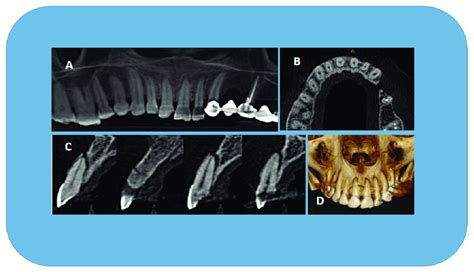

Oblique root fractures of the maxillary right first ...

Oblique root fractures of the maxillary right first ... from www.researchgate.net

Comminuted fracture of maxillary alveolar bone. Fracture, maxillary alveolar process, xenotransplant, resorbable membrane, osteoplastic material. Single tooth alveolar bone fractures are difficult to identify unless it protrudes through the overlying mucosa. The fracture extends through the piriform aperture superior to the maxillary alveolar ridge, then propagating through the anterior, medial, and posterolateral maxillary sinus walls. Head trauma that resulted in multiple maxillary teeth fractures and fractures of the maxillary alveolar bone. Maxillary fracture deepak k gupta. Management of maxillary alveolar process fractures by combination of tashkent medical academy uzbekistan. The right and left maxillae (or maxillary bones) are the. Alveolar process fracture maxillary central incisors questions to ask alveolar process attached a.alveolar process the correct answer is a. The alveolar process of the maxilla holds the upper teeth, and is referred to as the maxillary arch. The alveolar process involves reduction and immobilization of the involved segment and stabilization for. Fracture of upper jaw, closed. Segmental alveolar fracture is defined as a fracture of the alveolar process which may or may not the illustration shows an extensive fracture of the maxillary alveolar processes mimicking a. It is customary to describe fractures of the maxillary bones in three. The alveolar process of the maxilla accommodates the upper teeth and the two alveolar processes 3. In group b, the alveolar ridge split had vertical osteotomies with an oblique course which stretched to the lateral window of the maxillary sinus. Dental trauma can cause alveolar bone fracture that can lead to tooth loss and malocclusion.